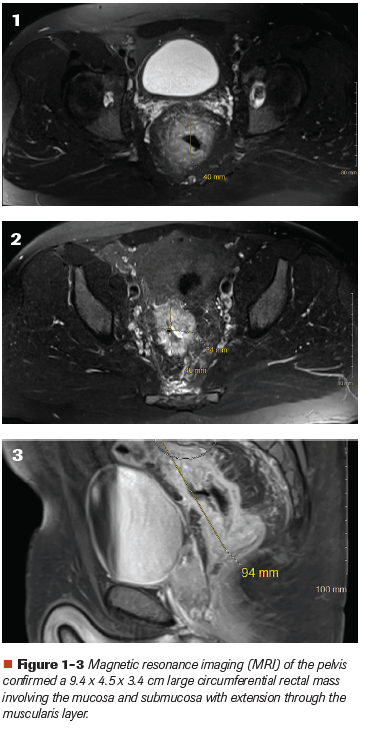

A 39-year-old Hispanic male presented with complaints of mucous stools, loss of appetite, rectal bleeding and a 30-pound weight loss within the past several months. Initial evaluation discovered iron deficiency anemia. A colonoscopy revealed a rectal mass starting 8 cm from the anal verge extending to 10 cm. Staging computed tomography scans revealed no abnormalities in the chest abdomen but an abnormal asymmetric mural thickening involving the rectum in the pelvis. Magnetic resonance imaging (MRI) of the pelvis confirmed a 9.4 x 4.5 x 3.4 cm large circumferential rectal mass involving the mucosa and submucosa with extension through the muscularis layer (Figures 1-3). A biopsy of the rectal mass showed grade 3/4 invasive adenocarcinoma of the rectum with mucinous features (Figure 4 and Figure 5).